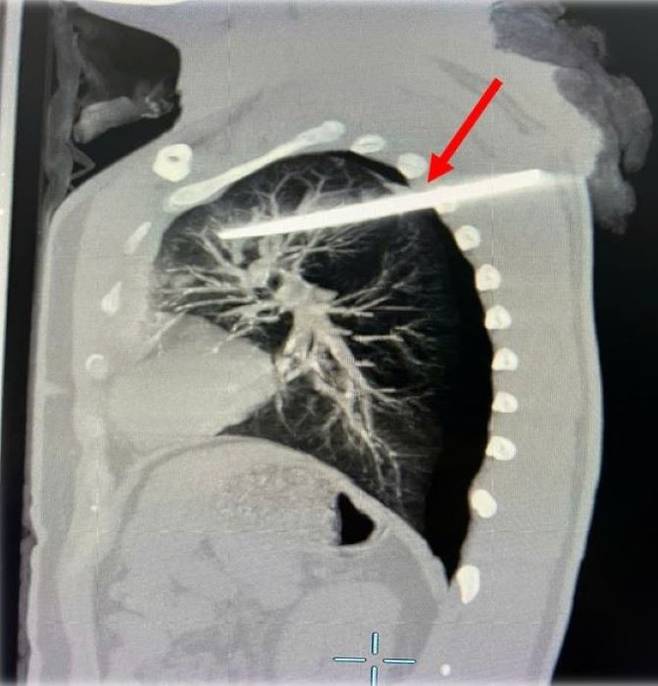

지난 6일(현지시각) 베트남 매체 자딘 닷 베트남에 따르면 베트남 하노이의 남성 A(29)씨는 밤에 길을 걷던 중 괴한에 의해 등 부위가 칼에 찔렸다. 그는 사고가 발생한 지 2시간 만에 108 국방부 중앙병원으로 이송됐다. 당시 A씨는 출혈성 쇼크로 인해 의식을 잃은 상태였다. 의료진은 엑스레이를 찍어 손상 정도를 파악했다. 검사 결과 왼쪽 폐에 구멍이 뚫렸다는 것을 확인했다. 의료진은 칼을 제거하고 손상된 폐를 봉합하는 수술을 진행했다. 108 국방부 중앙병원의 러쿠 트랭 의사는 “칼이 심장을 비켜갔고 신속하게 병원을 찾아 A씨는 살 수 있었다”며 “갑자기 칼이나 날카로운 물체에 찔리면 과다출혈로 인해 쇼크가 발생할 수 있다”고 했다. 이어 그는 “가능한 빨리 병원으로 이송되는 것이 중요한데, 살아날 확률을 80~90%까지 높일 수 있다”며 “조금만 늦었어도 A씨는 사망했을 수도 있다”고 말했다. 수술 후 A씨는 의식을 되찾았고 현재 중환자실에서 치료받는 중이다.